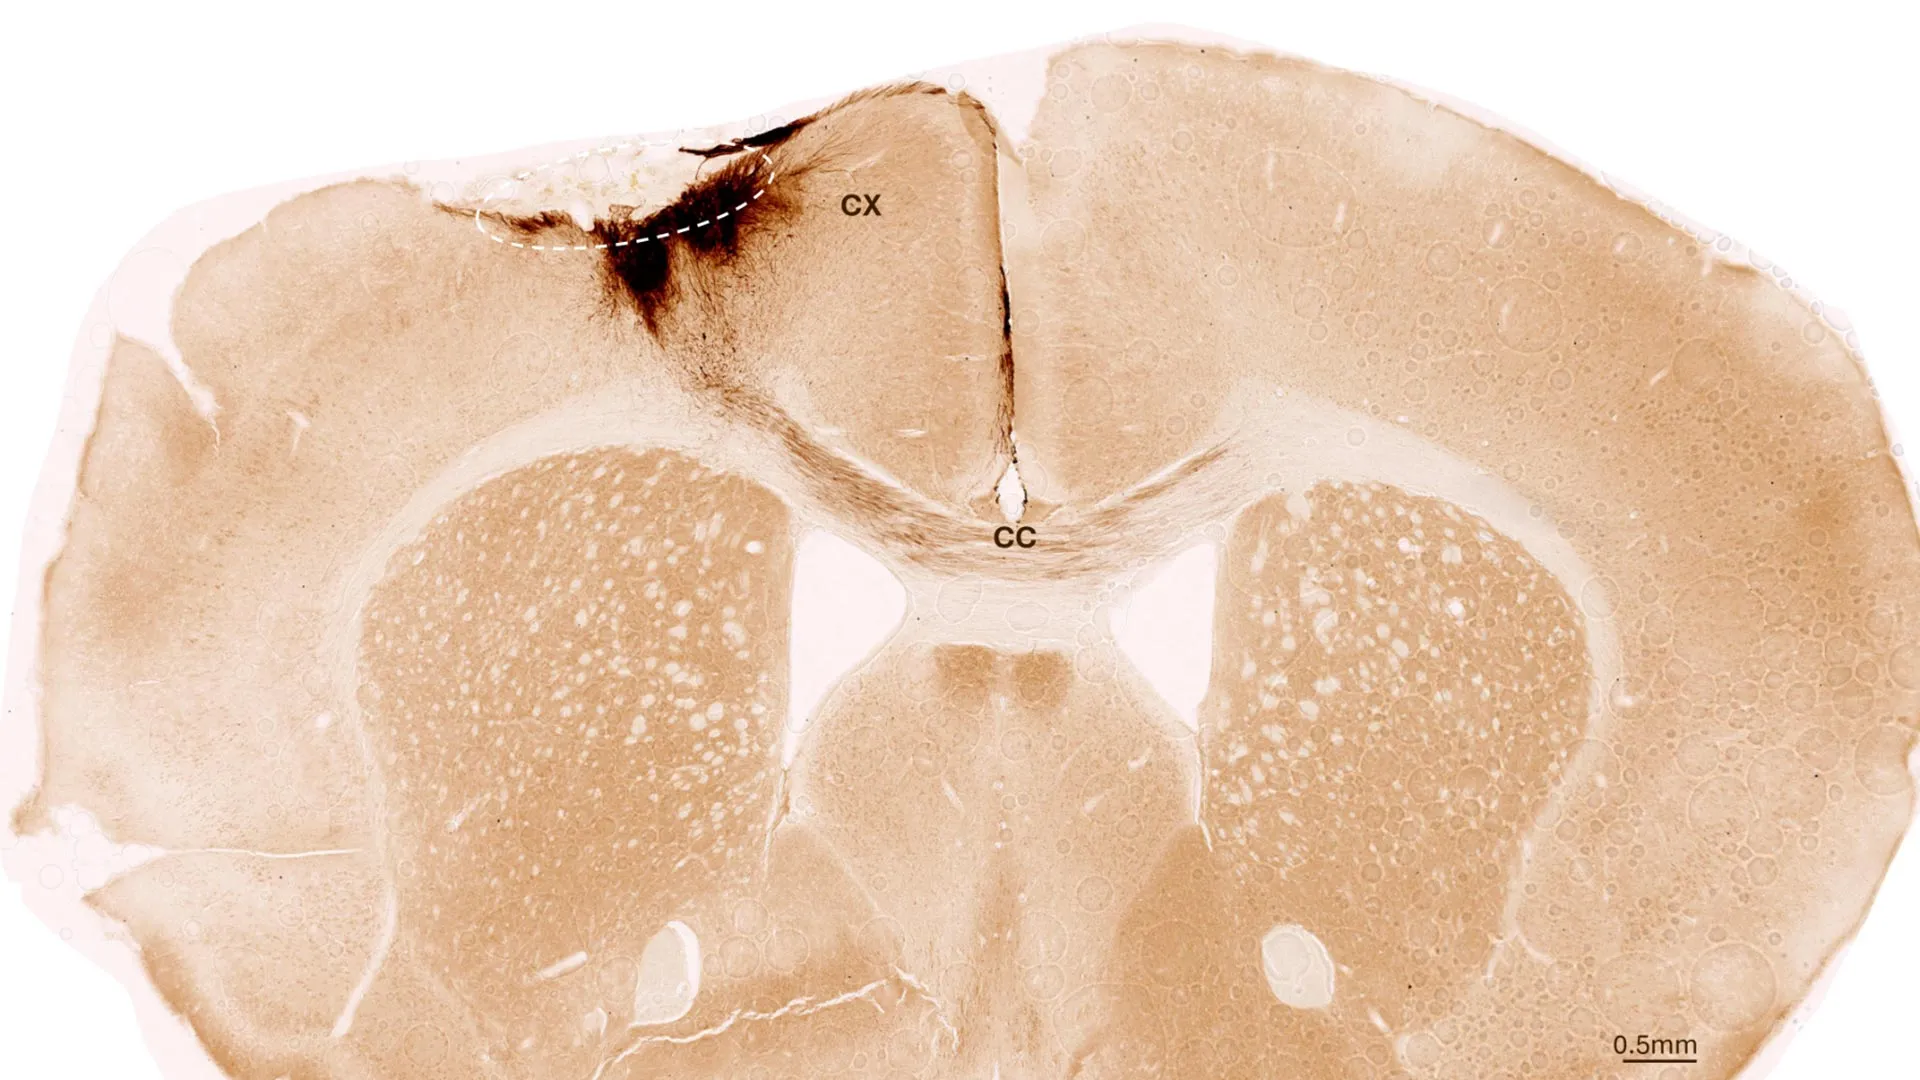

A recent study in mice suggests that restoring NAD+ levels with the compound P7C3-A20 can reverse brain damage and cognitive decline associated with advanced Alzheimer's disease, challenging the notion that the disease is irreversible. The findings highlight the potential for treatments targeting brain energy balance to repair damage and improve function, though further research in humans is needed.